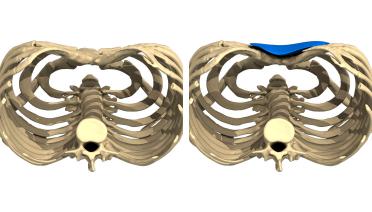

La tecnica di impianto su misura è una tecnica chirurgica minore che consiste nel riempire la concavità creata dal Pectus con un impianto personalizzato. Si tratta di un intervento rapido, a basso rischio, con un risultato immediato e una breve convalescenza.

In questa pagina, troverà i risultati di questa operazione a seconda del tipo di Pectus : mediale, asimmetrico, più o meno profondo o lungo.

Tipo 1 : Mediano, profondo e simmetrico,